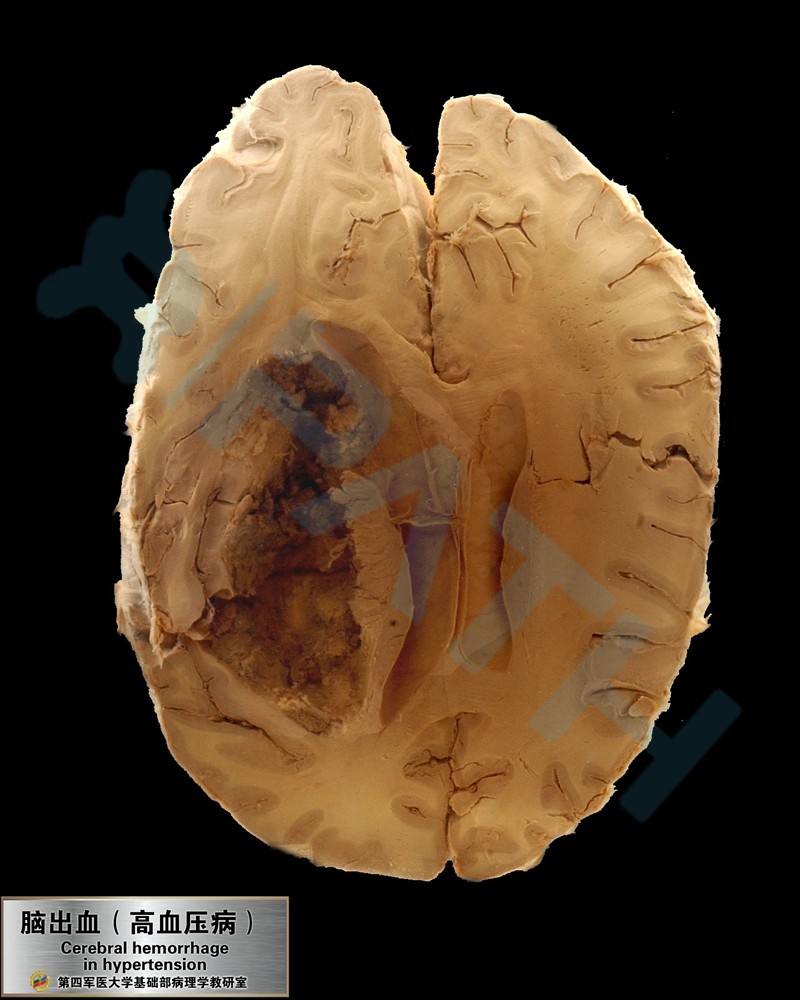

神经系统疾病

脑出血液化性坏死